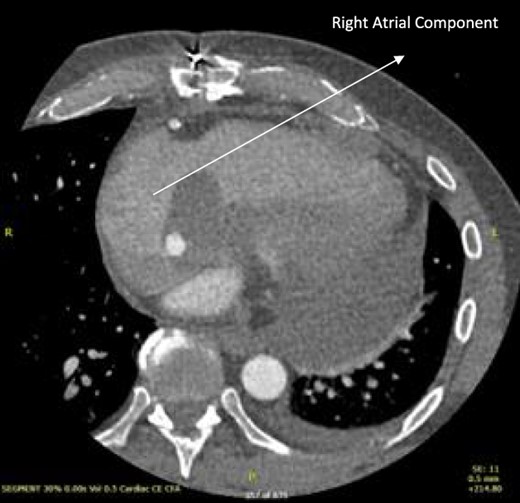

Follow-up CT scans were undertaken during chemotherapy that showed continued reduction in the size of the RA tumour, as demonstrated in Figs 4 and 5. The pericardial mass following chemotherapy is visualized in Fig. 6.

Post-operative CT scan showing further reduction of RA bulk following chemotherapy.